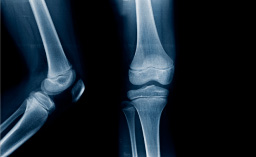

Diagnostic de l’acromégalie

Diagnostic de l’acromégalie – Peter Kamenicky